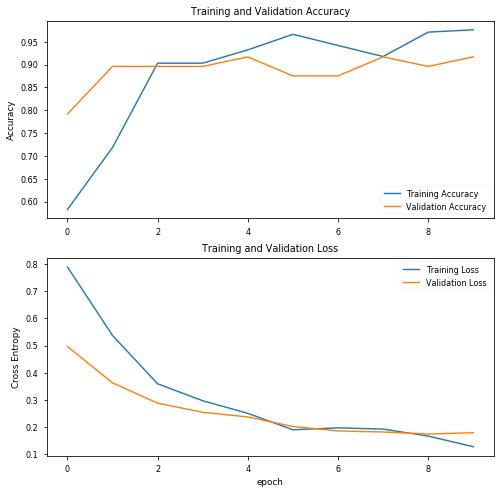

结果

precision recall f1-score support covid 0.93 1.00 0.96 27 normal 1.00 0.93 0.96 27 accuracy 0.96 54 macro avg 0.97 0.96 0.96 54weighted avg 0.97 0.96 0.96 54

以及混淆矩阵:

[[27 0] [ 2 25]]acc: 0.9630sensitivity: 1.0000specificity: 0.9259

结果好多了!现在具有93%的特异性,这意味着在没有COVID-19(即真反例)的患者中,在93%到100%的范围内我们可以准确地将他们识别为“COVID-19阴性”。

目前看来,这个结果很有希望。让我们保存这个模型,在那些没有经过训练的图像上测试(Covid-19的8个图像和从输入数据集中随机选择的20个图像)。

[INFO] evaluating network... precision recall f1-score support covid 0.93 1.00 0.96 27 normal 1.00 0.93 0.96 27 accuracy 0.96 54 macro avg 0.97 0.96 0.96 54weighted avg 0.97 0.96 0.96 54